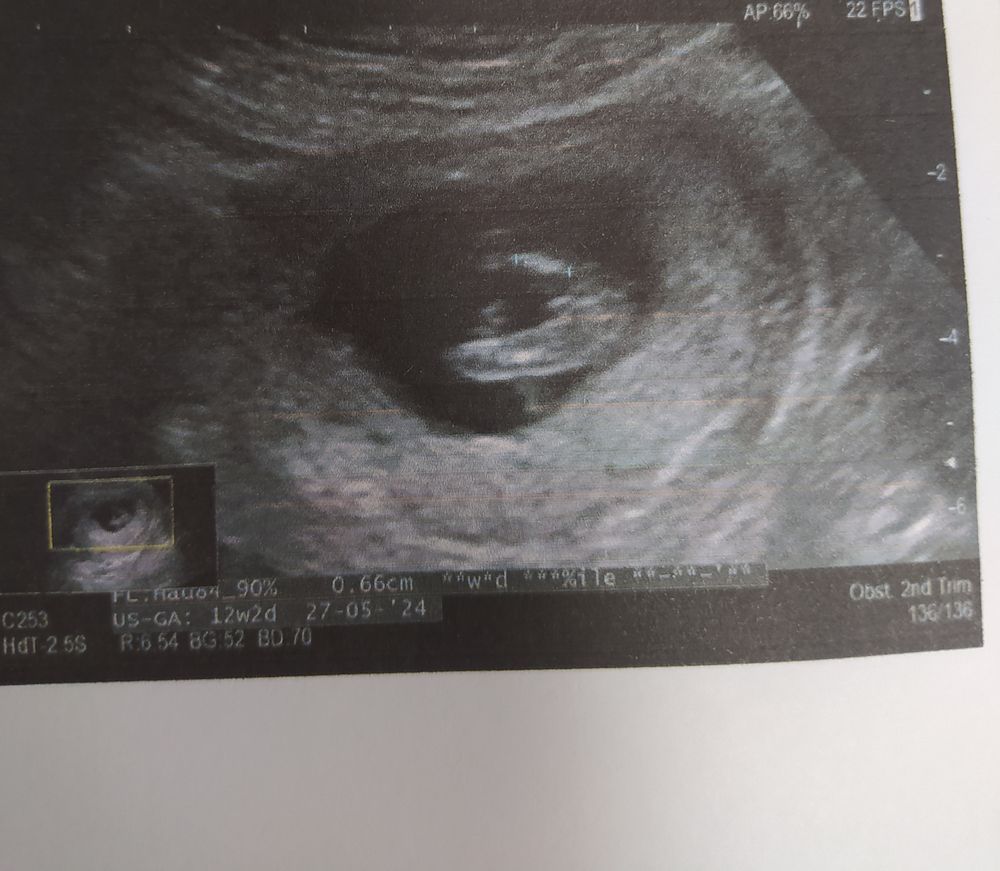

Девочка или мальчик ❤️💙

Вот наше узи в 12 недель снизу, врач предположил(!) девочку, но кружок сами видите какой Изображение А потому что нет у них там еще ничего, кроме бугорка

Узнали Пол🥰 УЗИ 12 недель